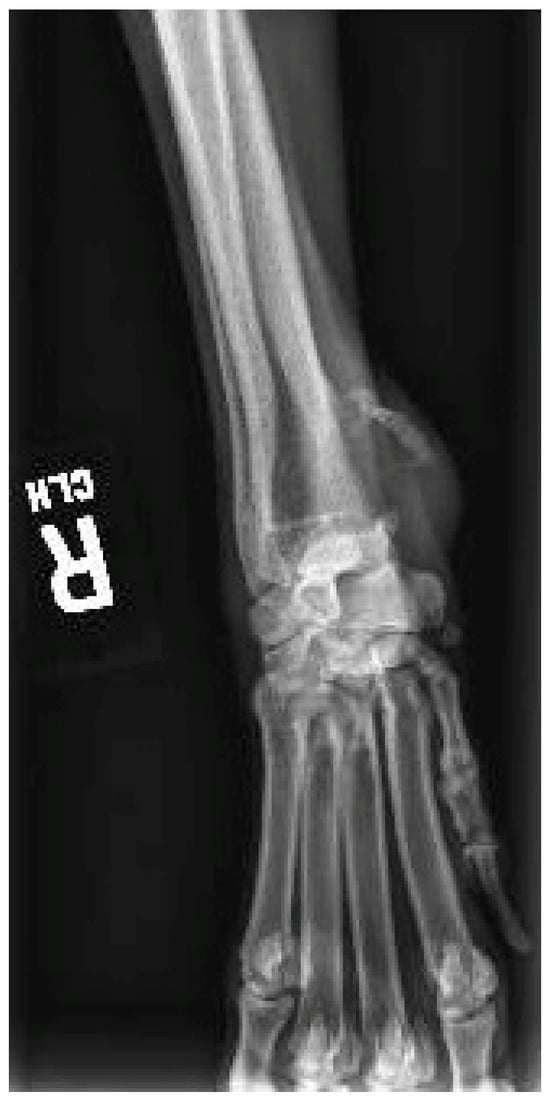

2. Case Description